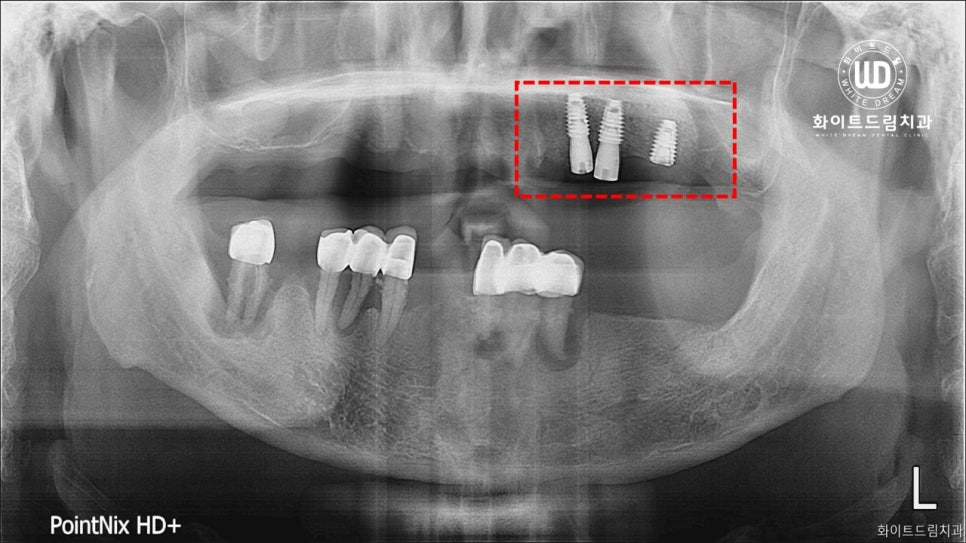

사진상으로 보시면 부분틀니를 오랫동안 사용하시면서 골 소실이 많고, 잇몸과 잇몸 뼈 주변까지 염증이 진행된 상태셨습니다. 전반적으로 구강 내 염증 정도가 심했고, 오랜시간 치아가 소실되어 있어 잇몸뼈 또한 녹아내린 상태였습니다.

이전의 케이스와 비슷하게 기존 보철물들은 제거가 필요한 상태였는데요. 환자분 동의 하에 남은 치아 전체 발치 후 상악 양측 구치부 상악동 거상술 및 뼈이식 진행 후 임플란트를 식립하는 임플란트 치료과정을 적용한 사례입니다.

상악동은 코 옆에 위치하고 하방으로는 위 어금니 치조골이 존재합니다. 하지만, 나이가 들어감에 따라 아래로 내려와 치조골 양이 조금씩 줄어들게 되는데요. 이러한 이유로 위턱의 작은 어금니와 큰 어금니가 빠진 경우 임플란트를 심을 치조골이 부족한 경우가 많습니다.

즉, 임플란트를 심을 뼈가 부족한 상태인 것을 확인할 수 있었습니다. 내원해주신 환자분께 상악동 점막을 들어올려 생긴 공간에 뼈를 이식하여 임플란트를 심을 수 있도록 도와드렸습니다.